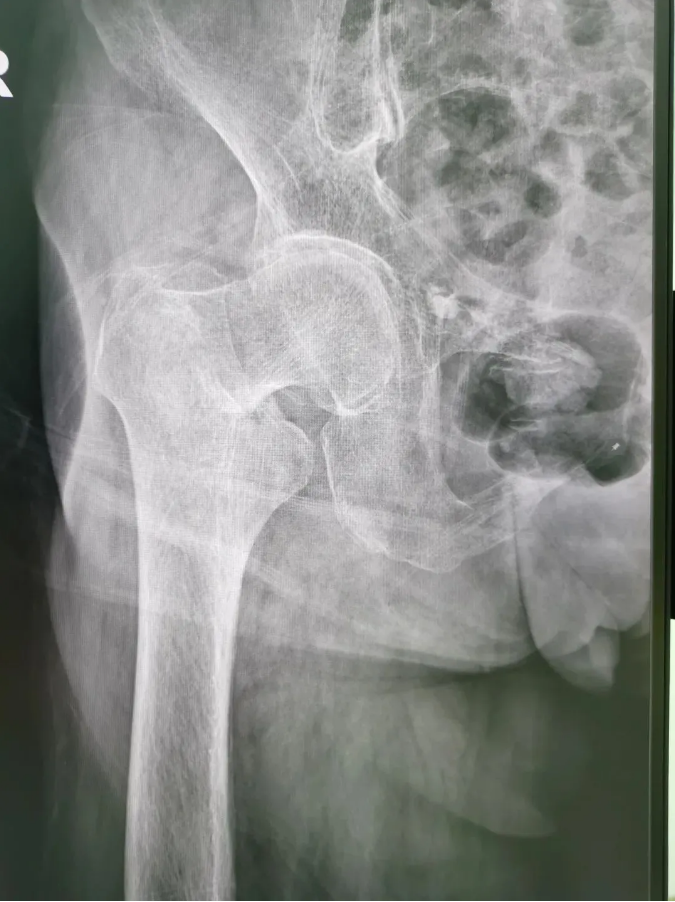

術(shù)前X光

陳婆婆91歲的高齡,有高血壓和冠心病病史,通過傳統(tǒng)開刀手術(shù)治療風(fēng)險(xiǎn)較大。經(jīng)骨三區(qū)專業(yè)醫(yī)療團(tuán)隊(duì)討論,決定讓天璣?骨科機(jī)器人上場(chǎng),輔助完成微創(chuàng)手術(shù)。